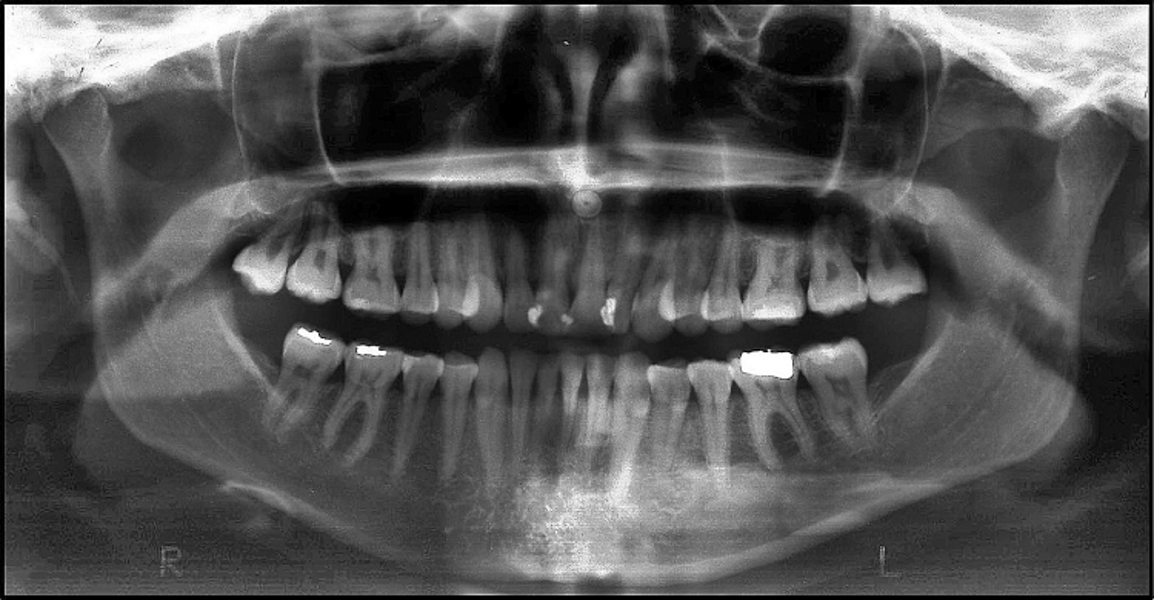

BiTurbo2 system for rapid deep overbite correction